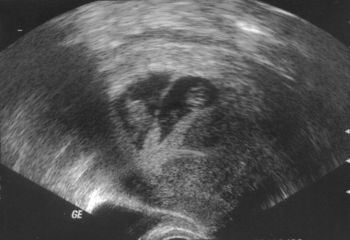

Tegnap megvolt a 12. hetes, uh, nagy élmény volt most is! Férjem is bent volt, a nőci tök jól megmutogatott mindent! BPD 22 mm, nyaki redő 1,8 mm. És hihetetlenül ficánkolt! Fel-le húzogatta a térdét! Mutatom a fotót is, hátat fordított nekünk, szépen látszik a gerince, meg a popója......... :lol:

Kép